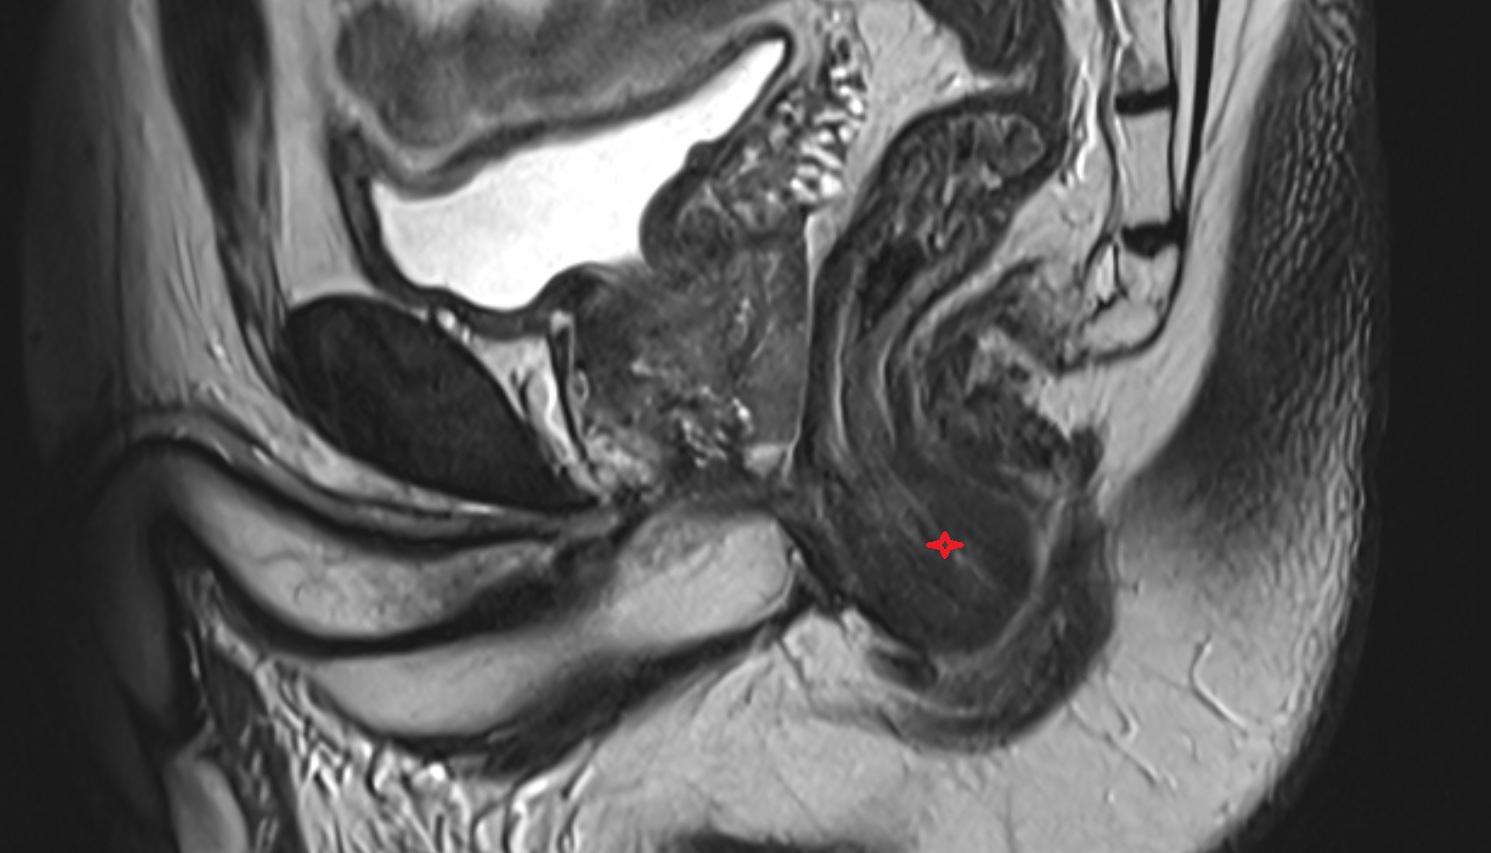

- Uterus

- Body of uterus

- Fundus of uterus

- Cervix of uterus

- Isthmus of uterus

- Vagina

- Fornix of the vagina

- Endometrium of uterus

- Myometrium of uterus

- Perimetrium of uterus

- Junctional zone of uterus